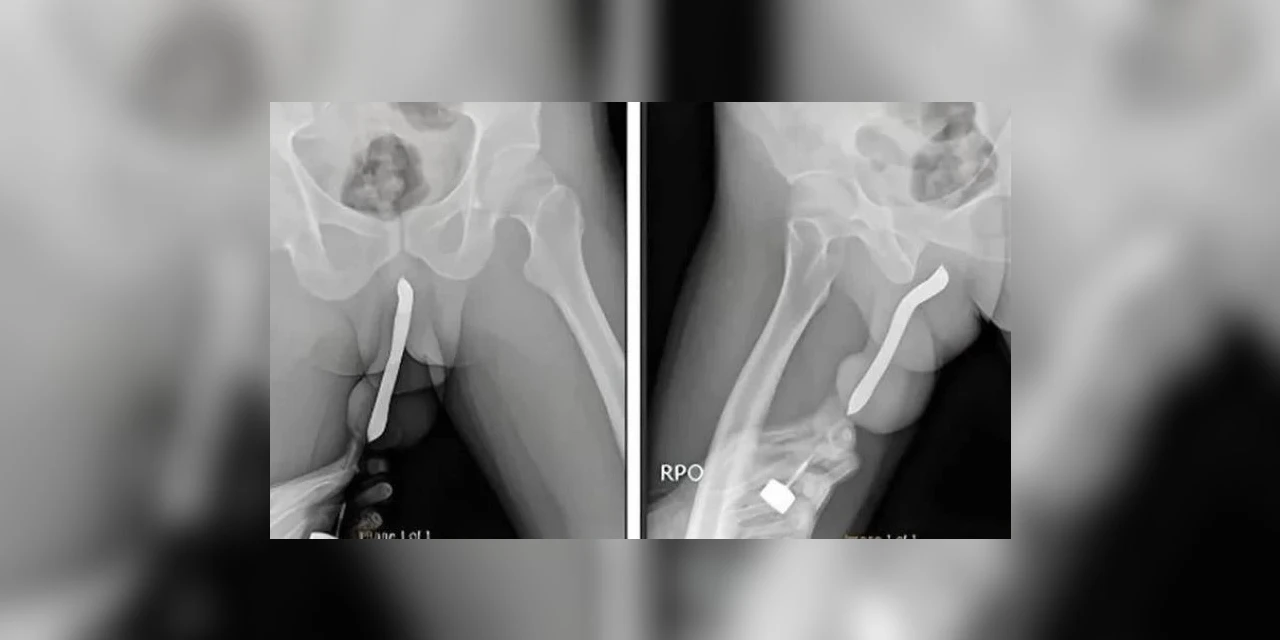

Revista 'International Journal of Surgery Case Reports'. - Foto: Reprodução / Redes Sociais

Um um indonésio, de 43 anos, sofreu uma fratura no pênis após inserir uma escova de dentes no órgão para “satisfação sexual”. O caso foi relatado em um estudo publicado através de canais de comunicação.

O paciente, cuja identidade não foi revelada, chegou ao pronto-socorro aproximadamente doze horas após o incidente. Ele havia inserido a escova de dentes no pênis durante uma relação sexual, resultando na quebra do objeto.

Surpreendentemente, não foi a primeira vez que o homem se envolveu em tal prática. Segundo o relatório, ele tinha um histórico de autoinserção de escovas de dentes no dorso e ventre do pênis desde 2017.

O homem teria chegado no local apresentando sintomas como dor, inchaço e hematoma. Após a comprovação do objeto em seu corpo, ele passou por uma cirurgia de remoção e conseguiu se recuperar, recebendo alta três dias depois de ter realizado todo o procedimento.